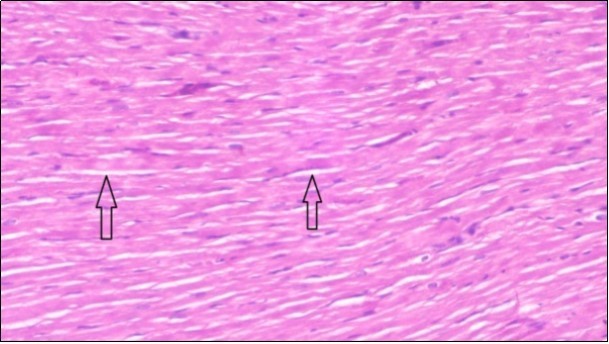

An important organ that is affected directly by the obesity which is the heart: The heart is the main important organ in circulatory system, the heart wall has three basic layers; the tunica intima of the heart is called endocardium, the tunica media of the heart is called the myocardium, the tunica adventitia of the heart the epicardium. The histological examination of the hearts of control rats feeding standard diet showing normal cardiac tissue with elongated, unbranched multinucleated muscle fibers (arrow), (Figure 1). The rats are feeding (HFD) for 2 weeks (obese rats) showing large number of inflammatory cells (star), degeneration muscles fiber ,circle and congested Blood vessels (arrow) (Figure 2). By comparison hearts of rats are treated by fennel after obesity and control rats observed show improved cardiac tissue with less infiltration (star) and well organized elongated muscle fibers with peripheral nuclei (arrow) (Figure 3). While examination of rats heart that treated by ator after obesity appears show less improved cardiac tissue with few inflammatory cells between disorganized muscle fiber (star), (Figure 4). While combined hearts of rats are treated by fennel and ator after obesity and control mice are showing nearly cardiac tissue with well-organized muscles fibers (arrow), (Figure 5).

Figure 5.Photomicrogragh of heart section of treated rat with both fennel herb and Ator drug showing nearly normal cardiac tissue with well-organized muscles fibers (arrow), (H&E) (400X).

These results were confirmed with histological changes of feeding rats heart tissues with high fat diet only, which showed vaculation of tunica media and narrowing in the lumen of aorta sections as well as congestion of cardiac blood vessel and hyalinosis of its wall. This result was confirmed by Szilvassy et al., 78, who indicated that although hyperlipidemia increases oxidative stress in the cardiovascular system, it renders the heart and the vasculature more susceptible to stress. Ouwens et al. 79 identified that development of hyper-cholestremia, which is one of the risk factors for cardio vascular diseases is associated with increased blood levels of TC, LDL-C and VLDL-C as well as lowered levels of HDL in rats fed on high fat-diet. This result was confirmed by histological study, which revealed apparent normal histological structure of heart in all treated rats with fennel seeds. Epidemiologic studies have shown an inverse correlation between HDL-C level and the risk of cardiovascular disease. Increasing the HDL cholesterol level by 1mg may reduce the risk of cardiovascular disease by 2 to 3 percent 80. The present data agreed with Fatiha et al. 81, who reported that hyper-lipidemic rats treated with fennel extract had significant decrease in plasma levels of TL, TG, TC, LDL-C and VLDL, and significant increase in HDL-C level. The current study demonstrates that the alteration induced by high fat diet causing changes in blood parameters. These changes are exhibited through a decrease in RBCs, Ht, Hb and platelet and these changes could be due to oxidative stress, which lead to lipid peroxidation in RBCs membranes, auto oxidation of hemoglobin. As regards the total WBCs, lymphocytes and monocytes showed a marked decrease. While a distinct increase in the percentage of neutrophils and esinophils. The present, demonstrates that rats treated with (fennel), (ator) and (fennel with ator) exposure provided significant protection to the altered haematological variables. The effect of the treatment with fennel and ator is more effective than fennel only or ator only. The current study showed that the serum levels of the total protein and albumin in the obese group were significantly higher than those of the control group. The administration of (fennel) revealed significant decrease in the serum levels of the albumin and total protein as compared to the obesity group, although the serum levels of the albumin and total protein of the Ator group less than the obesity group. Otherwise, the levels of the total protein and albumin in fennel and Ator group were near to the similar value of the control group. The finding of this study indicates that the concentration of Malondialdehyde (MDA) and Myeloperoxidase (MPO) in liver homogenates of the fennel and ator group significant decrease than group (3) and group (4) and obesity group. There is a growing awareness that obesity is a prime risk factor for the development of dyslipidemia profile and that oxidative stress may play a role in various adverse effects of obesity.